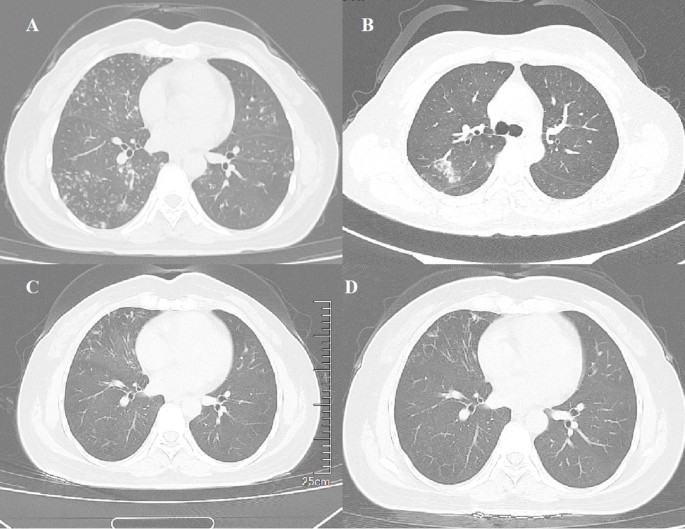

Mycobacterium hainanense sp. nov. represents an emerging nontuberculous Mycobacterium associated with chronic pulmonary disease

Clinical presentation and disease progression

A 42-year-old female power plant worker was admitted to our respiratory department on August 1, 2021, due to a recurrent cough and sputum production that had persisted for over eight years and worsened…